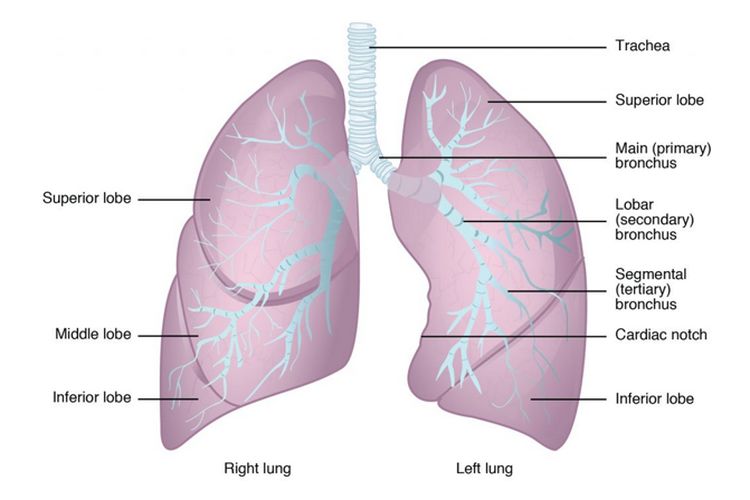

Paru-paru berfungsi sebagai organ utama dalam sistem pernapasan yang memungkinkan terjadinya proses respirasi. Melalui proses ini, oksigen dari udara dihirup dan dialirkan ke dalam aliran darah, sementara karbon dioksida sebagai sisa metabolisme dikeluarkan dari tubuh. Proses ini berlangsung secara otomatis dan terus-menerus tanpa disadari.

Udara yang masuk ke dalam paru-paru akan melewati saluran pernapasan hingga mencapai alveolus, yaitu kantung udara kecil yang memiliki dinding sangat tipis. Di sinilah pertukaran gas terjadi secara efisien. Struktur alveolus yang luas memungkinkan penyerapan oksigen dalam jumlah besar sekaligus membuang karbon dioksida secara optimal.

Salah satu fungsi paru yang paling krusial adalah melakukan pertukaran gas antara udara dan darah. Oksigen yang dihirup akan berdifusi melalui dinding alveolus ke dalam kapiler darah, kemudian diikat oleh hemoglobin untuk diedarkan ke seluruh tubuh. Proses ini menjadi dasar bagi metabolisme seluler.